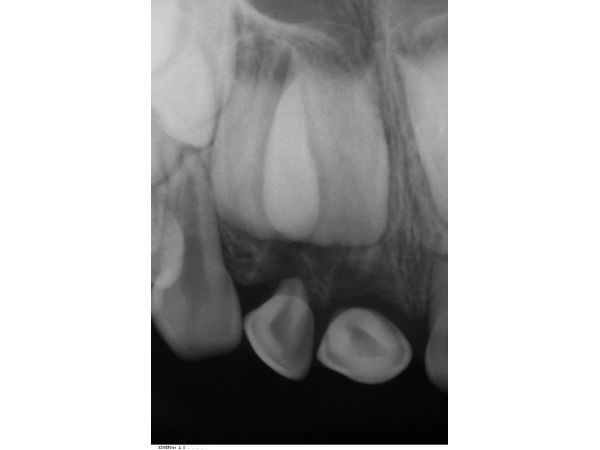

По результатам прицельной рентгенограммы, в лунках правых верхних резцов корней не было. Она также показала перелом в верхушечной трети корня левого центрального резца.

Перелом корня зуба 61, полный вывих (экзартикуляция) зубов 51 и 52.

Через четыре недели пациентке удалили шину и провели рентгенологический контроль: воспаления в области корня зуба 61 не было.

Спустя год ситуация стабильная: отломившийся кусочек корня 61 зуба разрушился.